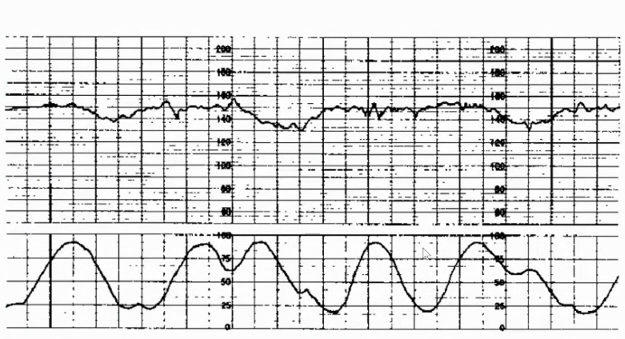

5.胎心率减速——晚期减速:胎心率缓慢降低,缓慢恢复正常,减速开始及恢复晚于宫缩,从开始到胎心率最低点时间≥30秒。产前出现一般提示胎盘功能不良,但是临产后尤其是第二产程出现偶发晚期减速不要过于紧张。

胎监cst是什么【温故知新】熟悉电子胎心监护判读要点,正确掌握胎监图纸解读六步法_https://www.jmylbn.com_新闻资讯_第3张

胎监cst是什么【温故知新】熟悉电子胎心监护判读要点,正确掌握胎监图纸解读六步法_https://www.jmylbn.com_新闻资讯_第28张